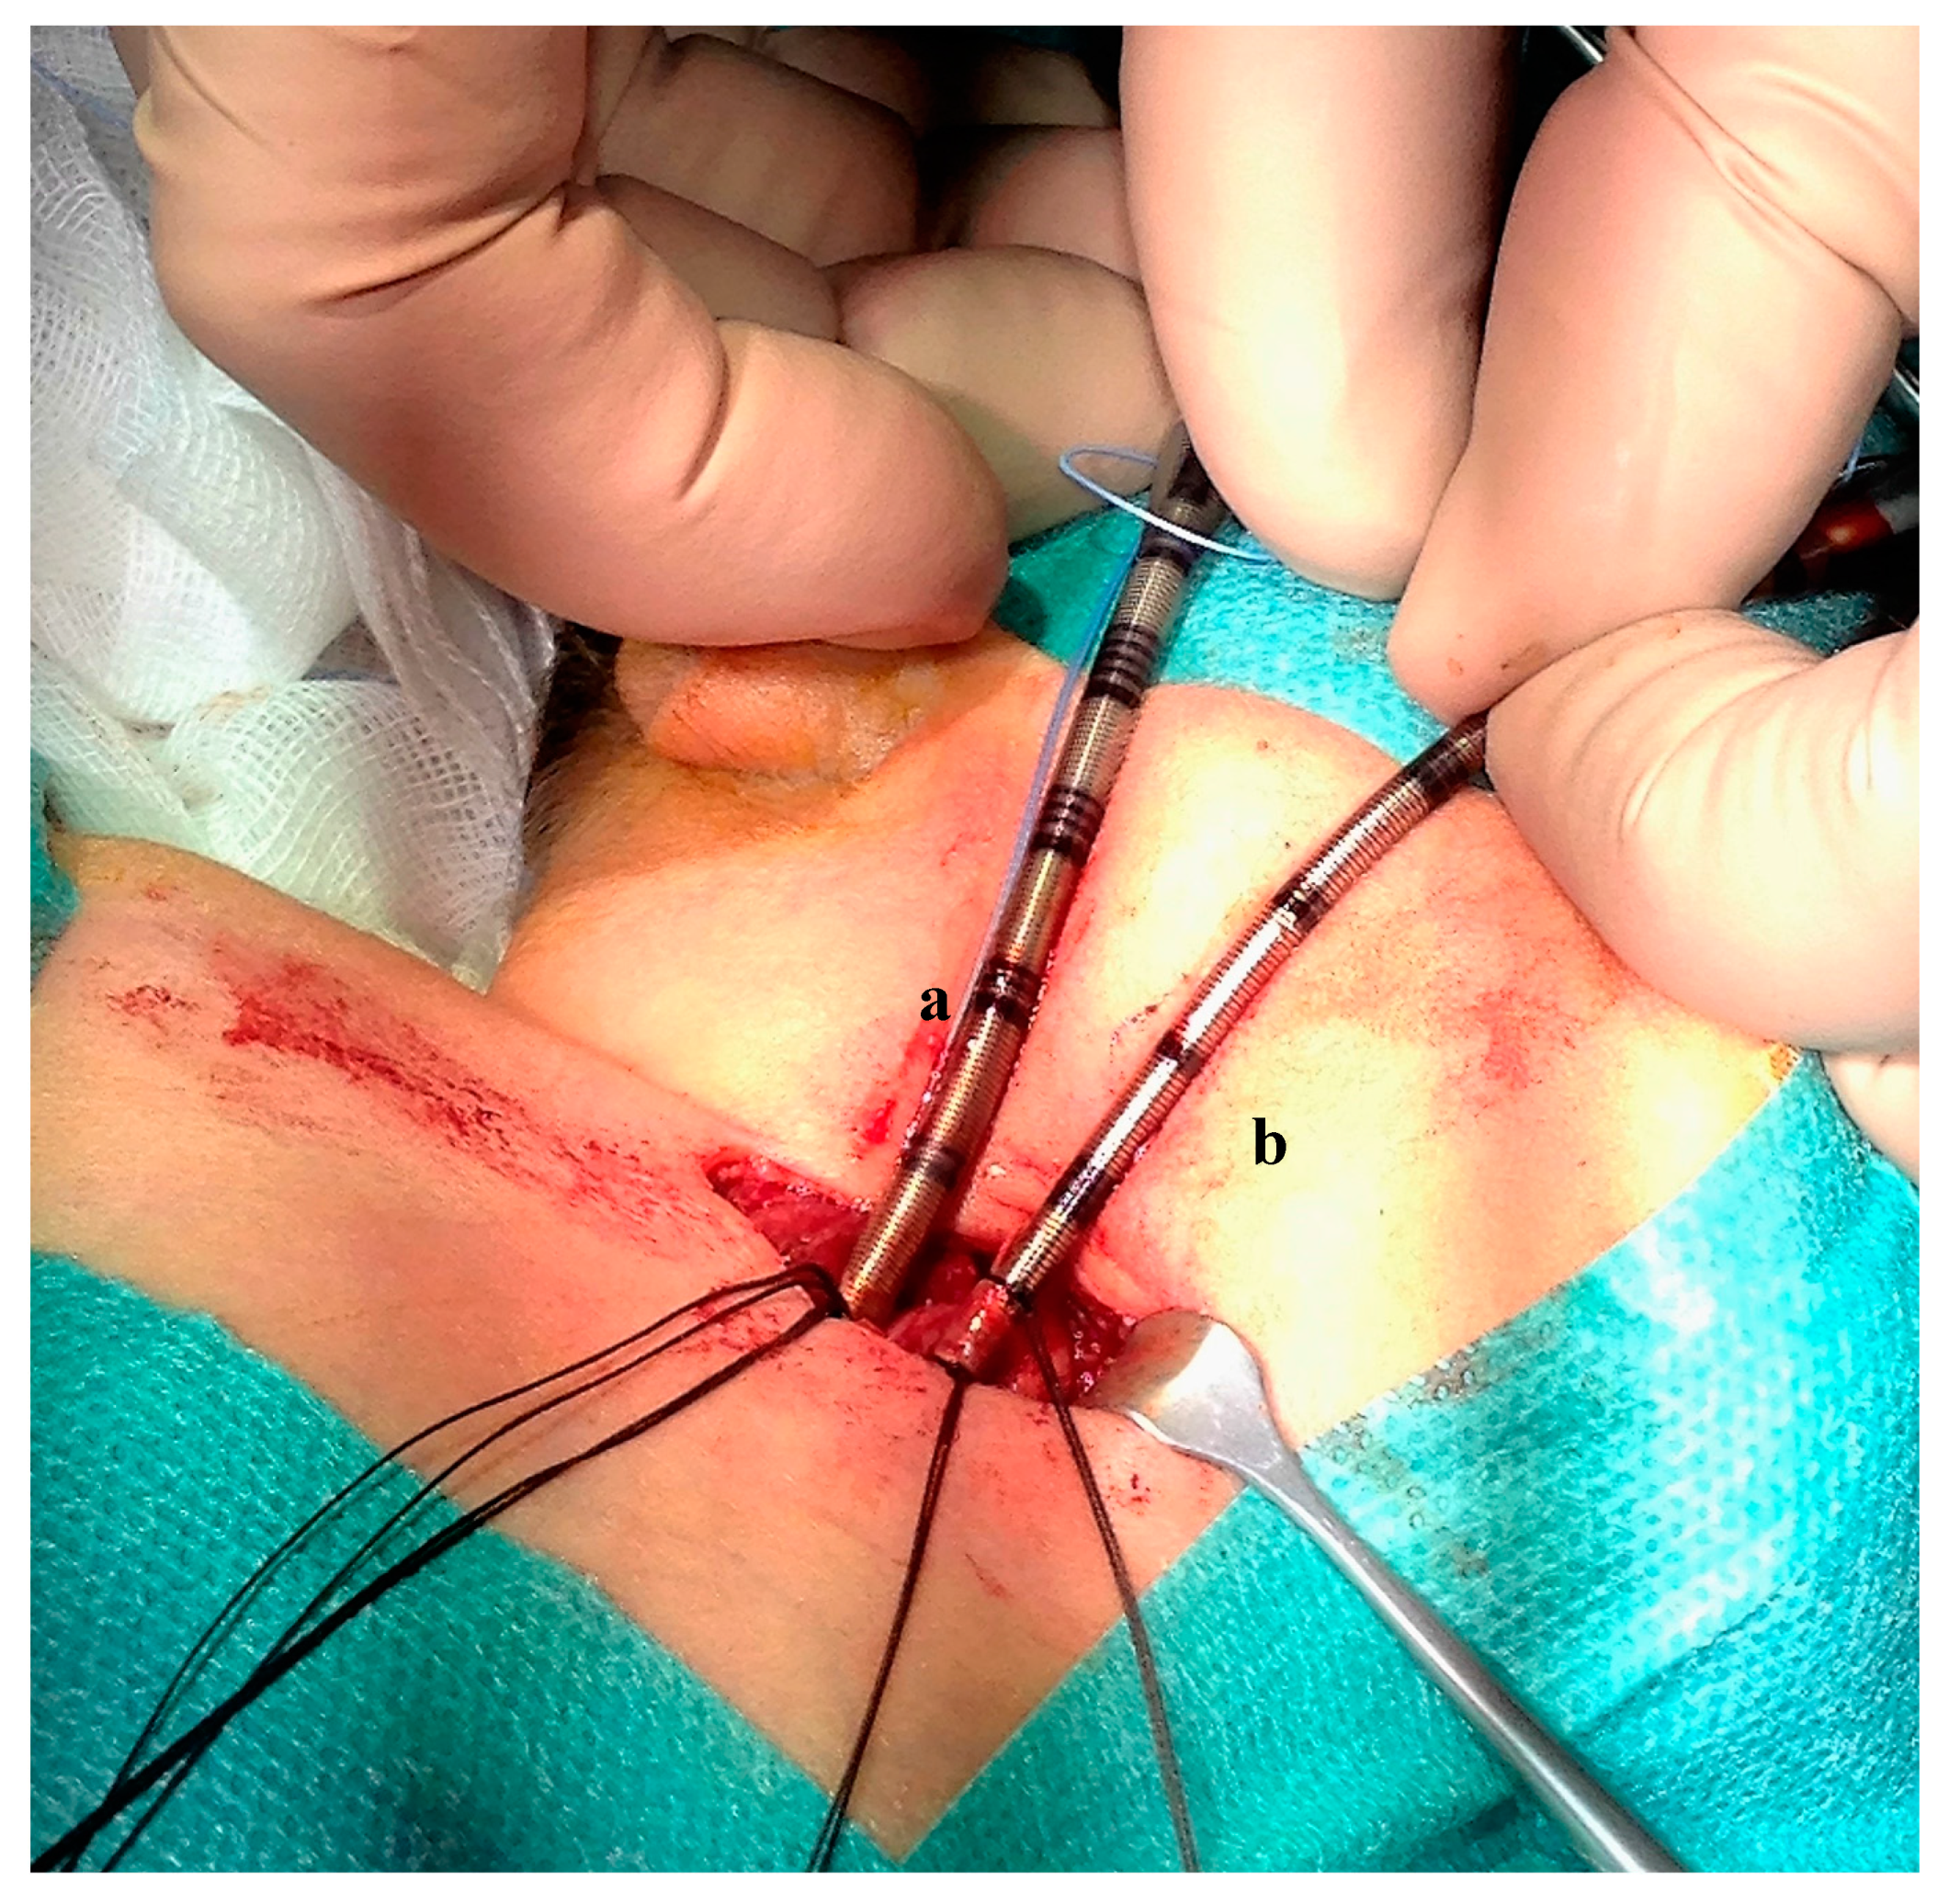

The patient weighed 3300 g at the beginning of the procedure. Surgical open cannulation was performed via the neck vessels, through a surgical exploration and dissection of the vessels (Figure 1). Correct cannula position was confirmed by chest X-ray (Figure 2) and trans-thoracic echo. Cardiopulmonary bypass (Quadrox iD, Maquet Getinge®) was established from the right internal jugular vein (10 Fr Medtronic®) to the right carotid artery (8 Fr Medtronic®), maintaining a blood flow of 350–500 mL/min (Cardiac Index 120–150 mL/kg/min).

Figure 1.

Peripheral extracorporeal life support. Surgical cannulation site in the neck: drainage cannula (10 French) inserted in the jugular vein (a), inflow cannula (8 French) inserted in the carotid artery (b).